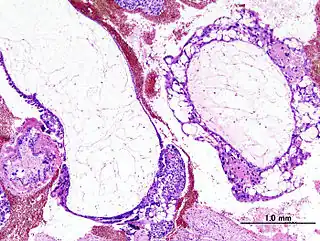

![]() Imagen histopatológica de la mola hidatiforme. | ||

La mola hidatiforme o embarazo molar es un trastorno del embarazo caracterizado por el crecimiento anormal de vellosidades coriónicas. Es una de las presentaciones de la enfermedad trofoblástica gestacional y se considera la forma no invasiva de esta. Mientras que en las molas completas no existe tejido embrionario, en las parciales se suelen hallar restos de un embrión no viable.[1][2] El tratamiento es terminar el embarazo molar tan pronto se haya hecho el diagnóstico por razón al alto riesgo que le acompaña una aparición de una forma de cáncer llamado coriocarcinoma.

Una mola se caracteriza por un producto de la concepción con tejido trofoblástico hiperplásico que rodea la placenta. El embrión no contiene la masa celular interna que caracteriza un embrión normal.

Si bien la enfermedad puede detectarse mediante una ecografía, el diagnóstico final se da mediante un examen patológico. En el ultrasonido, el útero parece tener un racimo de uvas, ya que así luce el embrión al anidarse.